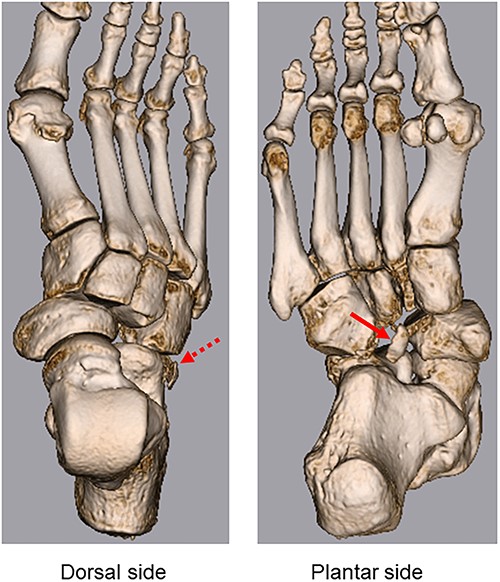

3D CT shows lateral dislocation of the naviculocuneiform and calcaneocuboid joints of the right foot, with fractures of the anterior edge of the calcaneus (broken arrow) and medial edge of the cuboid (arrow).

Midtarsal injuries tend to occur following high-energy trauma, namely, a traffic accident or fall from a height [4]. Previous studies have reported that these injuries were frequently overlooked or misdiagnosed [1]. Midfoot injury can negatively influence social aspects such as work and recreational activities. Therefore, early diagnosis and treatment of these injuries are required to avoid instability, long-term functional problems, foot pain and severe complications. History of the injury and physical examination is important for diagnosis. The most common symptom is severe pain; additionally, foot deformity can be masked by marked localized swelling on physical examination [4]. Since the injury tends to occur as a result of high-energy trauma, damage to other parts of the body should also be considered. In addition to plain radiography, CT is useful in diagnosing injuries; 3D CT provides more detailed images to diagnose small fractures and bone fragments [4]. In the present case, small fractures of the medial edge of the cuboid and anterior edge of the calcaneus were diagnosed using 3D CT (Fig. 3).